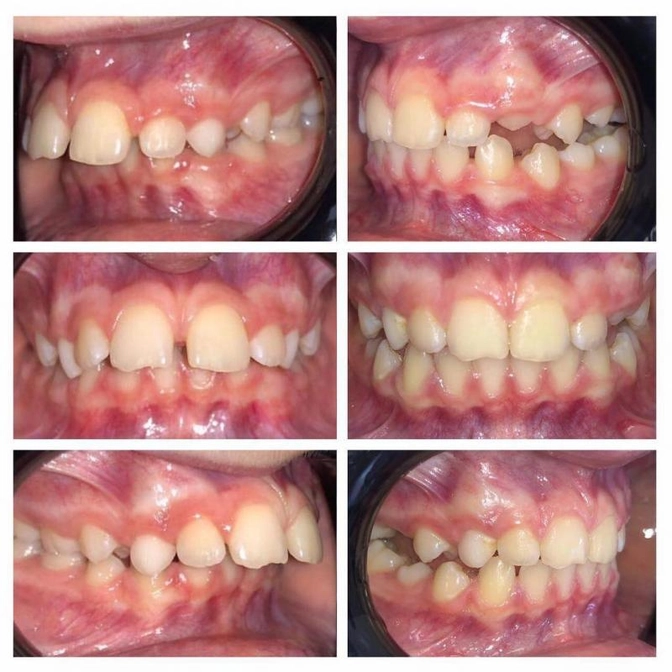

Работа нашего ортодонта Оксаны Журавской.

Умнице-пациентке 10 лет.

Начали ортодонтическое лечение в августе 2018 года, в коллаже динамика за 9 месяцев - результат супер!

Диагноз - дистальная окклюзия (нижняя челюсть задвинута назад) и протрузия резцов на верхней челюсти (торчат вперед, и, таким образом, образуется щель между нижними и верхними резцами).

Причины: доооолгое сосание пустышки - до 4х лет! А дальше присоединилось прикусывание нижней губы, что еще сильнее спровоцировало заднее положение челюсти.